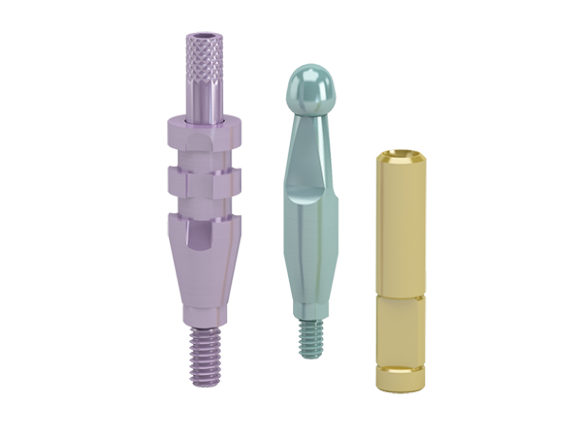

Conical Seal Design – a strong and stable fit

A conical connection that seals off the interior of the implant

from surrounding tissues, minimizing micromovements and microleakage.

Connective Contour – increased soft tissue contact zone and volume

The unique contour that is created when you connect the abutment to the implant.